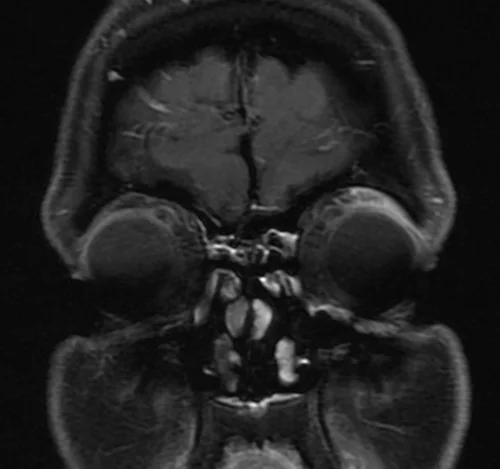

MRI Orbits coronal T1 fat sat images